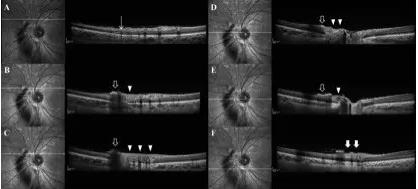

图 2 为患者 1 周后 OCT 检查:视网膜增厚,上方见高反射区及伪影

两周后,患者左眼视力上升至 6/9.5。眼底检查显示视网膜水肿有所好转,出血有所吸收(图 3)。OCT 显示视网膜水肿及视网膜前出血(图 4)。FA 示视盘鼻上侧低荧光,晚期鼻侧上方血管着色。ICG 显示相应区域低荧光(图 5)。

香港大学眼科学系案例:警惕激光操作不慎导致眼底损伤

图 3 为患者两周后眼底检查:视网膜水肿好转,出血有所吸收

图 4 为 OCT 显示视网膜水肿及视网膜前出血

图 5:A 为眼底自发荧光示损伤区低荧光;B~D 为 FA 造影示损伤区高荧光及着色,附近由于视网膜前出血导致低荧光;E~F 为 ICG 示损伤区脉络膜荧光减低,周边视网膜出血导致低荧光